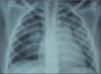

Las pruebas complementarias mostraron hemograma normal en las tres series, así como las pruebas de coagulación, bioquímica, iones y equilibrio ácido-base. La radiografía lateral de cuello fue normal y en la de tórax se apreció un patrón alveolar parahiliar bilateral (fig. 1). Los hallazgos de la tomografía computarizada (TC) de tórax fueron coincidentes con los de la radiografía, aunque algo más extensos (fig. 2). Estos datos eran compatibles con hemorragia pulmonar bilateral tras contusión pulmonar.

La imagen radiológica típica de la contusión consiste en infiltrados alveolares adyacentes al área del impacto, edema pulmonar y, en ocasiones, fracturas costales, si bien éstas pueden no hacerse evidentes hasta 48h después de la contusión4. En nuestro caso, la radiografía de tórax presentó imágenes compatibles desde el inicio.